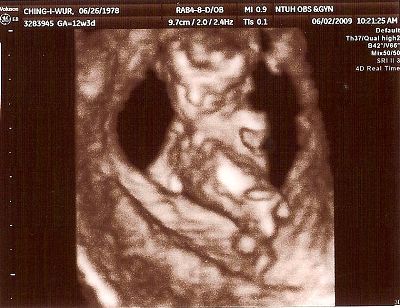

12W2D醫生安排照頸部透明帶

老愛趴著的娃娃,讓我只得在醫院長長的走廊來回不停地走

一直不斷跟他溝通快快轉過來

好不容易可以照了

醫生帶著我數著娃娃的手指頭,1、2、3、4、5

看看四肢、心臟 、屁屁等器官

看著娃娃揮舞著四肢可愛的模樣,好感動好感動

隨著時間的經過,大概也有三十分鐘了吧!

醫生左搖右晃地還沒結束

心中正納悶著

結果醫生說鼻骨好像不是很清楚

有百分之六十的唐寶寶有這個情況

頓時,心都涼了一截

在醫生的說明下,叫我別太擔心,因為還要看抽血及整體的評估報告

拿了超音波照片的我,帶著一顆忐忑不安的心離開醫院